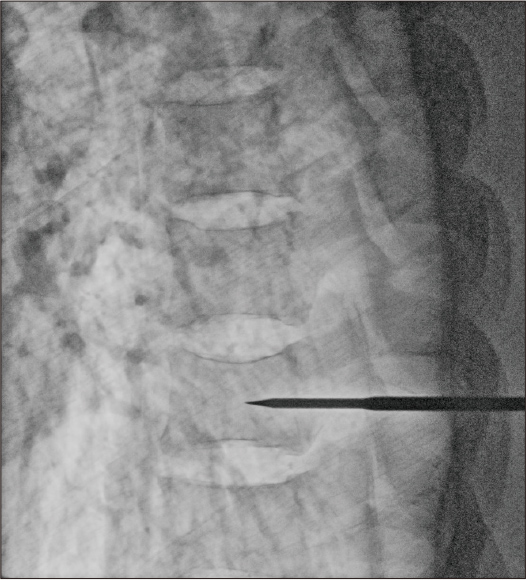

After applying Dynamic processing + noise reduction

Dose: 4.2mA

(FUJIFILM FDR D-EVO lll)